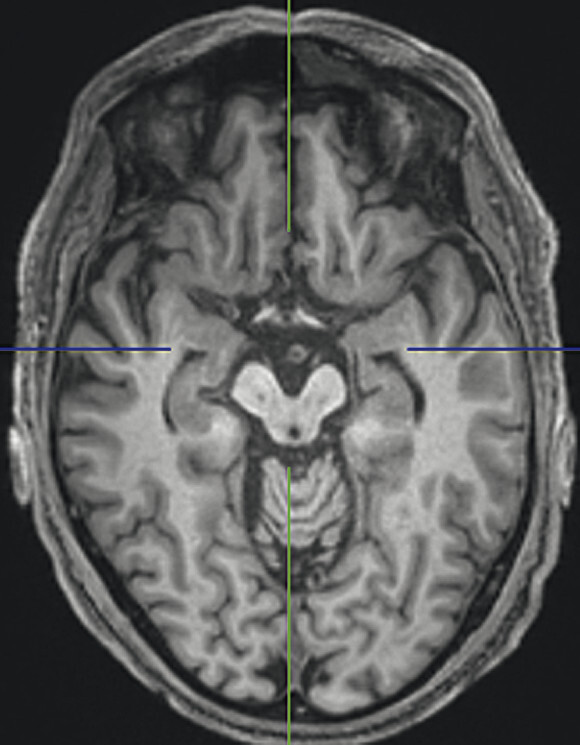

74-jähriger Patient mit linksbetontem Parkinson-Syndrom und aktuell deutlicher demenzieller Entwicklung mit exekutiver Störung und Zeitgitterstörung. In der T1w 3-D-MRT zeigt sich ein unauffälliges Mesenzephalon (a) mit einer normalen Midbrain/Pons-Ratio von 0,61 (kurzer Durchmesser des Mesenzephalons: 9,9 mm; kurzer Durchmesser des Pons: 16,1 mm, beide durch eine rote Linie dargestellt; b). Die automatisierte Ganzhirnvolumetrie (c) lässt außerdem ein anomales Hirnvolumen frontal bis parietal beidseits erkennen. In der 2 mm dünnen transversalen SWI-Schicht findet sich kein Schwalbenschwanzzeichen (d).

a T1w 3-D-MRT-Sequenz.

b T1w 3-D-MRT-Sequenz mit eingezeichneten Durchmessern.

c Ganzhirnvolumetrie.

d Transversale SWI.